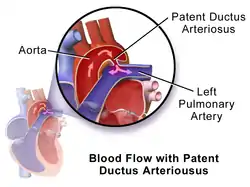

Illustration of Patent Ductus Arteriosus

Illustration of Patent Ductus Arteriosus Patent ductus arteriosus

Patent ductus arteriosus (PDA) is when the connection between the aorta and pulmonary artery (the ductus arteriosus) fails to close after birth.[3] Early on there are generally no symptoms; however, later shortness of breath, failure to gain weight at a normal rate, or difficulty exercising may occur.[1][4] Complications may include heart failure, pulmonary hypertension, necrotizing enterocolitis, kidney failure, and intraventricular hemorrhage.[2]

The cause is generally unknown.[1] Risk factors include premature birth, maternal diabetes, cocaine, calcium channel blockers, and birth at high elevation.[2] It is associated with a number of genetic syndromes including trisomy 13, Down syndrome, and DiGeorge syndrome.[2] The ductus arteriosus is a fetal blood vessel that normally closes within 24 to 48 hours after birth.[2] The diagnosis may be suspected based on a continuous heart murmur and confirmed by ultrasound of the heart.[2]